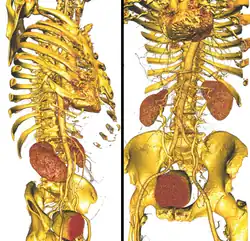

The Scientific Computing and Imaging (SCI) Institute is a permanent research institute at the University of Utah that focuses on the development of new scientific computing and visualization techniques, tools, and systems with primary applications to biomedical engineering.[1][2] The SCI Institute is noted worldwide in the visualization community for contributions by faculty, alumni, and staff.[3] Faculty are associated primarily with the School of Computing, Department of Bioengineering, Department of Mathematics, and Department of Electrical and Computer Engineering, with auxiliary faculty in the Medical School and School of Architecture.

The overarching research objective of the Scientific Computing and Imaging Institute is to conduct application-driven research in the creation of new scientific computing techniques, tools, and systems. Given the proximity and availability of research conducted at the University of Utah School of Medicine, a main application focus is medicine. SCI Institute researchers also apply computational techniques to scientific and engineering sub-specialties, such as fluid dynamics, biomechanics, electrophysiology, bioelectric fields, scientific visualization, parallel computing, inverse problems, and neuroimaging.

- ImageVis3D - volume rendering application with multidimensional transfer function visualization support

- Seg3D - interactive image segmentation tool